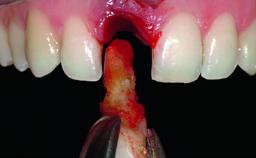

Replacement of a Compromised Upper Right Central Incisor: Hard- and Soft-tissue Augmentation, Late Placement of an RC Bone Level Implant

A 36-year-old male patient with a compromised maxillary central incisor was referred by his general dentist for consultation. The patient’s chief complaints were the gradual debonding of a temporary crown on the right central incisor and unsatisfactory esthetics due to an increasing diastema between the right central and lateral incisors. The patient reported a traumatic event some years previously, when a crown had been placed after root-canal treatment. The referring dentist wanted to provide a new crown restoration, but was concerned about the condition of the residual root. Anamnesis was negative for any other dental or periodontal pathology in the remaining dentition. The patient reported taking no medications: He was a smoker (10 to 15 cigs/day) and had realistic esthetic expectations.

Bone Augmentation Horizontal|Simultaneous|Staged

Augmentation Materials Xenogenous|Membrane

Bone Volume Deficient horizontally, requiring prior grafting